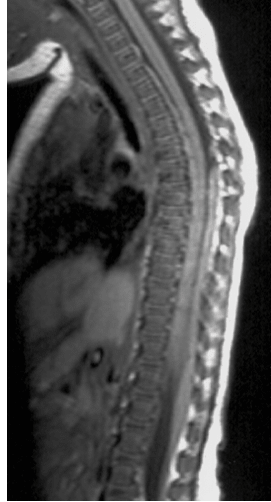

- l’étirement médullaire : la flexion-extension rapide et répétée entraine une étirement du rachis (c’est une forme de SCIWORA) et un épaississement du ligament jaune lors de l’hyper-extension avec rétrécissement du canal cervical (Cf. ci-contre)